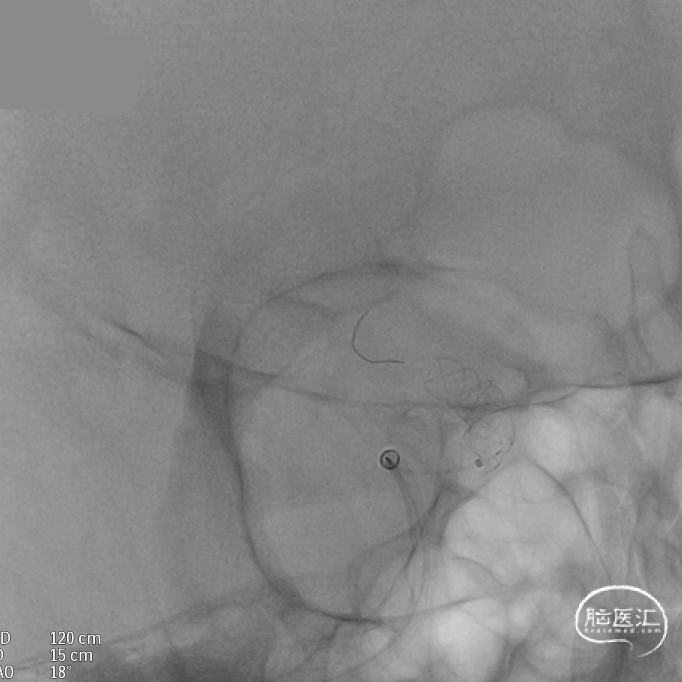

术后造影:支架覆盖两枚动脉瘤瘤颈,贴壁良好,瘤体内可见造影剂滞留。

术后支架显影: